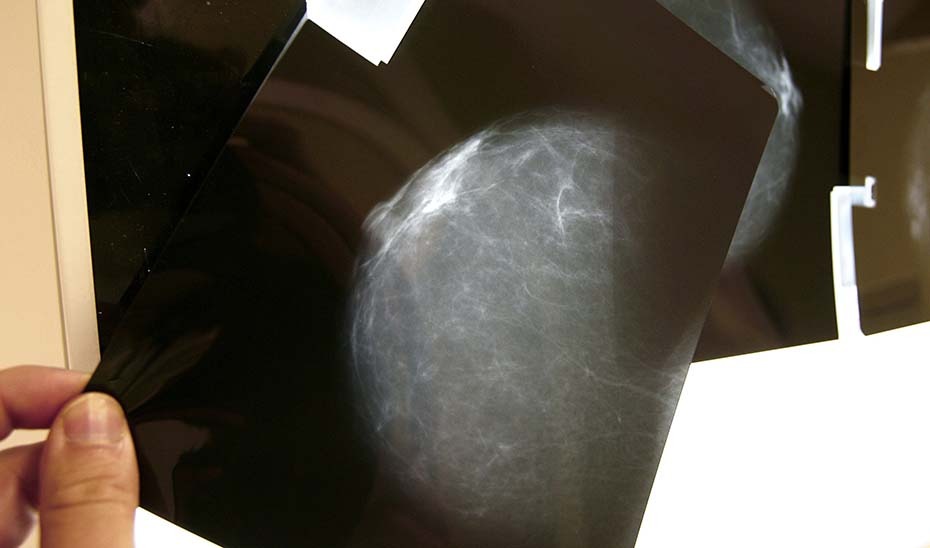

En el programa de cribado de mama, las mamografías pueden arrojar tres resultados: negativo, positivo o lesión posiblemente benigna. En este último caso, hasta tres radiólogos analizan las imágenes y determinan el intervalo para la segunda prueba según los factores de riesgo individuales. La falta de información inmediata generaba ansiedad, ya que las pacientes desconocían que su caso estaba bajo supervisión médica.

El programa de cribado de cáncer de mama en Andalucía, consolidado desde 1995, cubre actualmente a mujeres de entre 49 y 71 años, con una tasa de participación cercana al 70-75% y cobertura del 80% de la población diana. La estrategia ha permitido detectar sospechas radiológicas de cáncer de mama en unas 2.100 mujeres cada año.